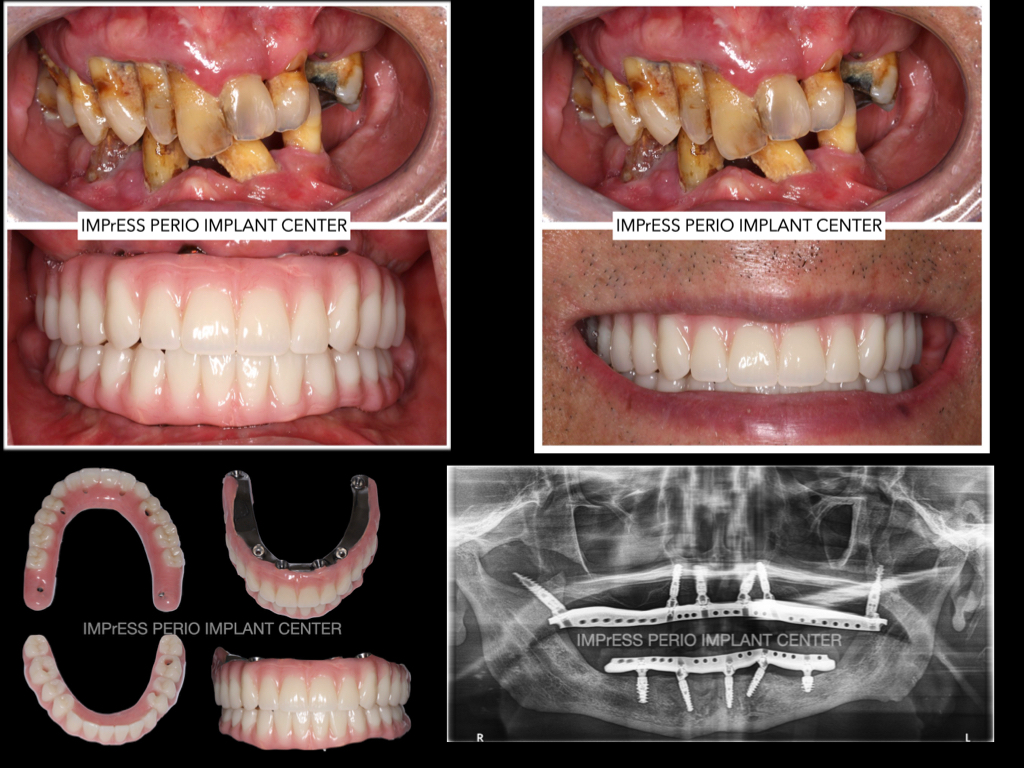

Full Mouth Reconstruction with Fixed Implant Bridge – All on X

All on X implant Full Mouth Implant Reconstruction All on 4 Implants IMPrESS Perio Implant Center Vancouver Burnaby Periodontist Prosthodontist Implant Specialist Dr. Noroozi Periodontist Implant Specialist

mile Makeover with Full Mouth Implants IMPrESS Perio Implant Center Burnaby BC Dr Noroozi

Full Mouth Implant Rehabilitation IMPrESS Perio Implant Center Dr. Noroozi implant Specialist Burnaby Vancouver BC

All On X Full Mouth Implants Fixed Teeth IMPrESS Perio Implant Centre Dr Noroozi Burnaby Vancouver BC

All on X Full Mouth Implant Rehabilitation IMPrESS Perio Implant Center Dr. Noroozi Implant Specialist Burnaby

All on X implant Full Mouth Implant Reconstruction All on 4 Implants IMPrESS Perio Implant Center Vancouver Burnaby Periodontist

Full Mouth Implant Restoration Burnaby Implant Specialist IMPrESS Perio Implant Center Dr. Noroozi

Full Mouth Implants IMPrESS Perio Implant Center Burnaby Vancouver BC Dr. Noroozi All On 4 Implants

3 on 6 implants Full Mouth Implants IMPrESS Perio Implant Center Dr. M. Noroozi Vancouver Implant Specialist

All on Four Implants Vancouver Burnaby BC Teeth in a day IMPrESS Perio Implant Center Dr. Noroozi

Best All on X Full Mouth Implants All On 4 Vancouver Dental Implants Dr. Noroozi IMPrESS Perio Implant Center Implant Specialist

Fixed Implant Teeth IMPrESS Perio Implant Center Dr. Noroozi Implant Specialist

Porcelain Hybrid Imlant Supported Fixed Bridge to replace all missing teeth Burnaby Vancouver BC

Xray of full mouth implants Vancouver BC